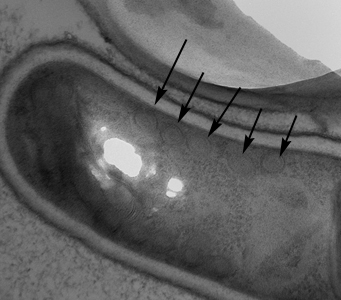

A 27-year-old HIV-positive male presented with abdominal pain and chronic diarrhea. He had a history of AIDS cholangiopathy. Recent microbiology results included bacteremia caused by Enterobacter species and sputum cultures positive for Mycobacterium avium-complex (MAC). During routine examination of Gram-stained bronchial alveolar lavage (BAL) specimens, suspect objects were observed by the attending technologist. Additional BAL material was stained with calcofluor white and Gram chromotrope, and the suspect objects were observed being positive for both. Images were captured of the BAL stained with Gram chromotrope (Figures A and B) and sent to the DPDx Team for diagnostic assistance. Additionally, the BAL specimen was forwarded on to the DPDx Team for additional work-up. The DPDx Team prepared a fresh smear from the BAL, stained with chromotrope 2R, and observed similar objects at 1000x with oil (Figures C and D), which measured approximately 2.0 micrometers in length. What is your diagnosis? Based on what criteria? What additional tests, if any, would you recommend?

Figure C

Figure D